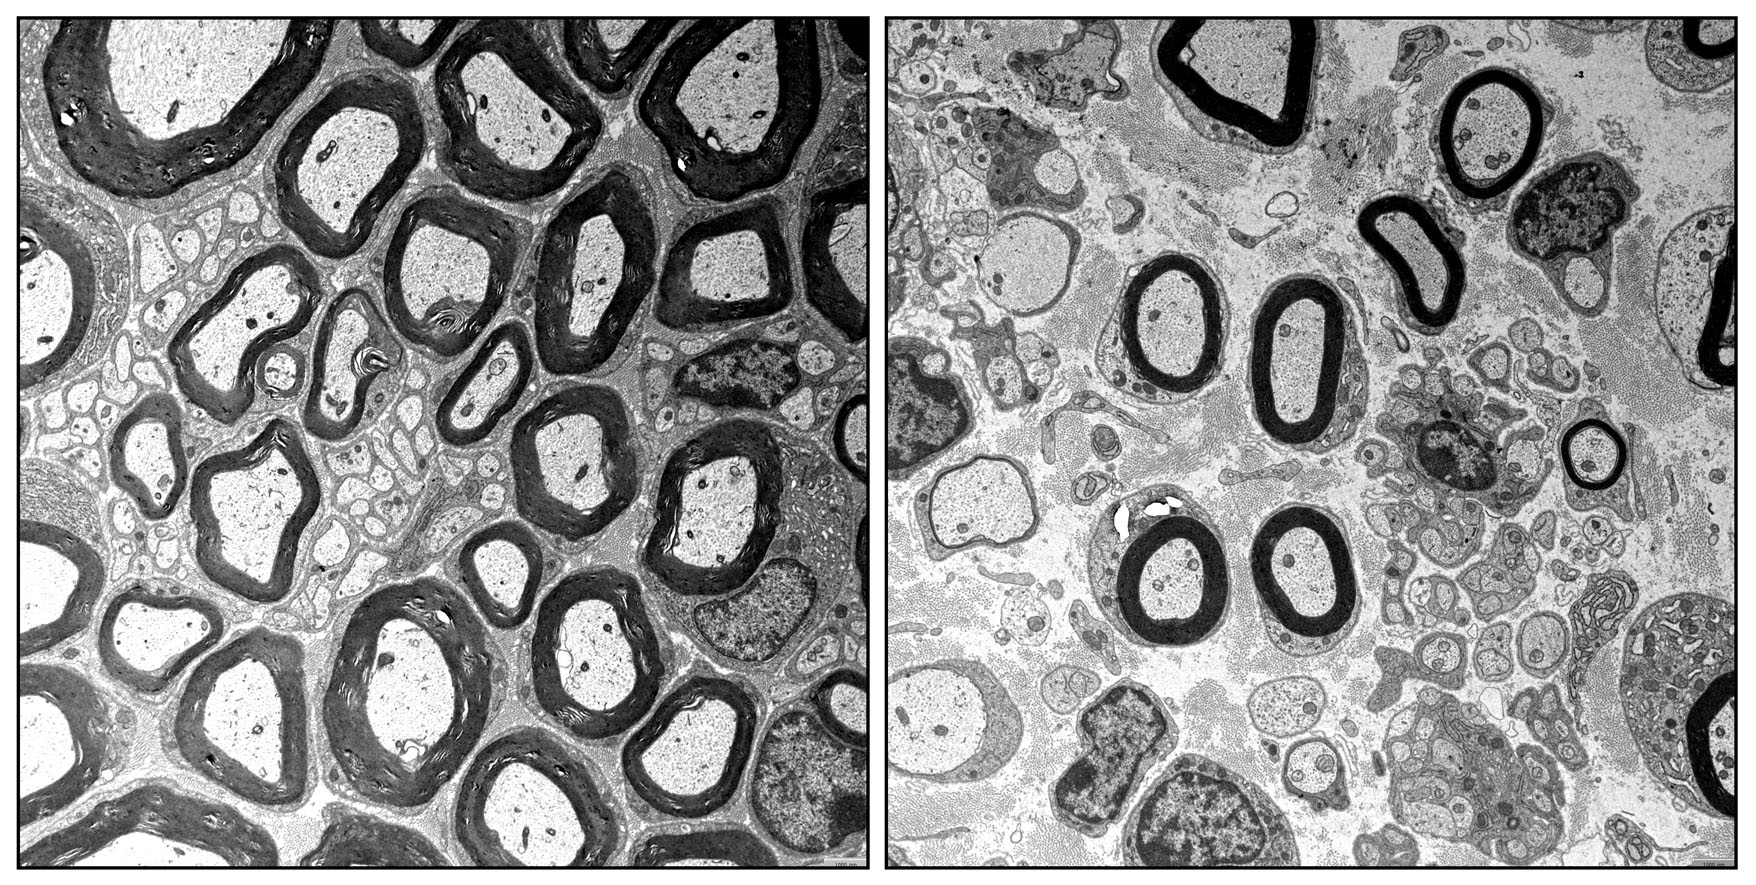

Der FAU-Arbeitsgruppe ist es nun zum ersten Mal gelungen, einen solch komplexen Zusammenhang aufzuklären. Im Mittelpunkt steht ein Eiweiß mit dem Namen „EP400“, dessen Vorkommen in Schwann-Zellen das Team erst kürzlich selbst entdeckt hat. Das Eiweiß sorgt in den Schwann-Zellen zusammen mit anderen Eiweißen dafür, dass die DNA richtig verpackt und mit Lesezeichen versehen wird. Das Verpacken ist immens wichtig, um die Erbinformationen möglichst kompakt im Zellkern unterzubringen. Die Lesezeichen erlauben das Auffinden und Ablesen der benötigten Informationen. In ihren Versuchen entfernten die Wissenschaftler das Eiweiß aus Schwann-Zellen. Daraufhin schaltete sich das Programm zur Zellentstehung nicht mehr korrekt ab und überlagerte das eigentlich folgende Reifungsprogramm, so dass einige nicht mehr gebrauchte Proteine unvermindert weitergebildet, andere benötigte Proteine aber nicht in ausreichendem Maß hergestellt wurden. Dies führte dazu, dass die Myelinscheiden der Schwann-Zellen nur mit Defekten ausreiften – sie waren zu dünn und kurz, entsprechend fehlerhaft die gesamte Schutzhülle der Nervenfasern. Als die Wissenschaftler eines der normalerweise durch EP400-regulierten, fehlerhaft weiter produzierten Eiweiße mit dem Namen „Tfap2a“ zusätzlich entfernten, verringerten sich die Defekte merklich.